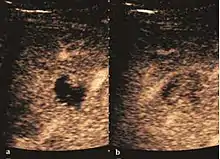

Dysplastic nodules (DN)

These lesions have various patterns (hypo or hyperechoic) with at least 1 cm diameter. They are hepatocytes with dysplastic changes, but without clear histological criteria for malignancy. They are divided into low-grade dysplastic nodules, where cellular atypia are mild and high-grade dysplastic nodules with moderate or severe cellular atypia, but without any established signs of malignancy. Occasionally, well-differentiated HCC foci can be identified in high-grade dysplastic nodules (appearance called "nodule in nodule") . Most authors accept the carcinogenesis process as a progressive transformation of DN from low-grade to high-grade and into HCC. The nodule's vasculature changes progressively, correlated with the degree of malignancy, and it is characterized by decrease until absence of portal venous input and by increase of arterial intratumoral input. Neoformation vessels occur with increasing degree of dysplasia. Arterial neovascularization is enhanced in a chaotic and explosive way, while normal, arterial and portal vasculature continues to decline. High-grade dysplastic nodules are hypovascularized both arterial and portal phases, while early HCC nodules may have similar arterial pattern with the surrounding parenchyma or exacerbated, and portal hypovascularization. In moderate or poorly differentiated HCC (classic HCC) tumor nutrition is performed only by neoformation vessels (abundant), the normal arterial and portal vasculature completely disappearing. This behavior of intratumoral vascularization is typical for HCC and is the key to imaging diagnosis.

B-mode ultrasonography is unable to distinguish between regenerative nodules and borderline lesions such as dysplastic nodules and even early HCC. Doppler examination also has a low sensitivity in differentiating dysplastic nodules from early HCC. Doppler signal may be absent in both regenerative and dysplastic nodules. Some authors indicate the presence of venous type Doppler flow which reflects the portal venous nutrition of the nodule as a characteristic feature of dysplastic nodules and early HCC (Minami & Kudo, 2010). Other authors noticed the presence of an arterial flow with small frequency variations and a normal resistivity index. On CEUS examination both RN and DN may have quite a variable enhancement pattern. Generally, both nodules enhances identically with the surrounding liver parenchyma after UCAs injection. Dysplastic nodules are hypovascular in the arterial phase. In case of highgrade dysplastic nodule sometimes a hypervascularization can be detected, but without associating "wash out" during portal and late CEUS phases. In these cases, biopsy may clarify the diagnosis.